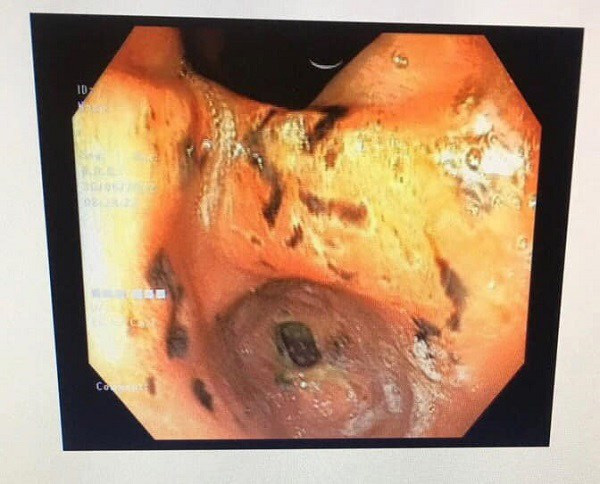

Theo Arttimes dẫn lời bác sĩ Đào Thị Ánh Tuyết (Bệnh viện Đa khoa huyện Thạch Thất) cho biết, bệnh viện vừa tiếp nhận và điều trị cho một bệnh nhi (10 tuổi, ở Bình Phú, Thạch Thất, Hà Nội) nhập viện vì bị hoa mắt, chóng mặt 3 ngày liên tục. Thăm khám lâm sàng cho thấy, trẻ có biểu hiện da xanh, niêm mạch nhợt, mạch nhanh, huyết áp thấp.

Trước những biểu hiện trên, các bác sĩ đã tiến hành đặt sonde dạ dày phát hiện ra dịch nâu, thăm hậu môn trực tràng có phân đen theo găng. Trẻ nhanh chóng được làm các xét nghiệm máu, siêu âm và chụp Xquang ổ bụng, nội soi dạ dày kiểm tra.

Kết quả cho thấy trẻ có tình trạng thiếu máu nặng do xuất huyết tiêu hoá do có nhiều ổ loét vùng tá tràng. Bệnh nhân được điều trị đặt sonde và bơm rửa dạ dày, cầm máu, truyền máu, sử dụng thuốc giảm tiết acid. Khi nhận kết quả, bố mẹ cháu bé vô cùng choáng váng vì trước đó trẻ chưa từng mắc bệnh hay biểu hiện bất bất thường gì.

Sau 03 ngày điều trị tích cực, hiện trẻ có da niêm mạc hồng, bắt đầu ăn cháo nguội, tình trạng cải thiện hơn. Tiến hành nội soi lại kiểm tra vết loét đã cầm máu ổn định các xét nghiệm công thức máu có cải thiện rõ rệt.